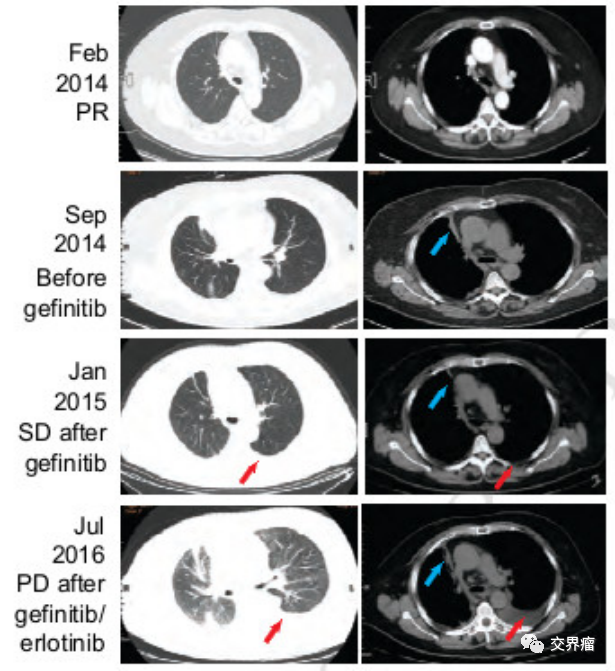

2.基因检测显示患者出现C797S继发突变

在对奥希替尼耐药的患者进行的基因检测中,C797S继发突变是常见的耐药突变,占比15%-20%。分顺势突变和反式突变,多以顺势突变为主。对于T790M/C797S反式突变的患者,可以采用奥希替尼+吉非替尼即三代+一代的处理方案。但对于T790M/C797S顺势突变的主要耐药人群,需要采用西妥昔单抗+布加替尼。下图是一位顺势导致耐药患者的处理案例。

患者62岁女性,接受化疗——一代EGFR靶向治疗——奥希替尼治疗——奥希替尼耐药——发现T790M/C797S顺势突变——采用布加替尼(90mg/日)+西妥昔单抗(600mg/月),治疗一个月时,患者呼吸困难明显改善,病灶缩小。